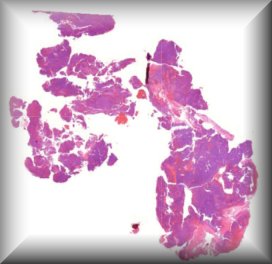

Susan Kennedy: Exenteration specimen of a 70-year-old female who underwent multiple (14) surgeries for conjunctival melanoma over a period of two years. |